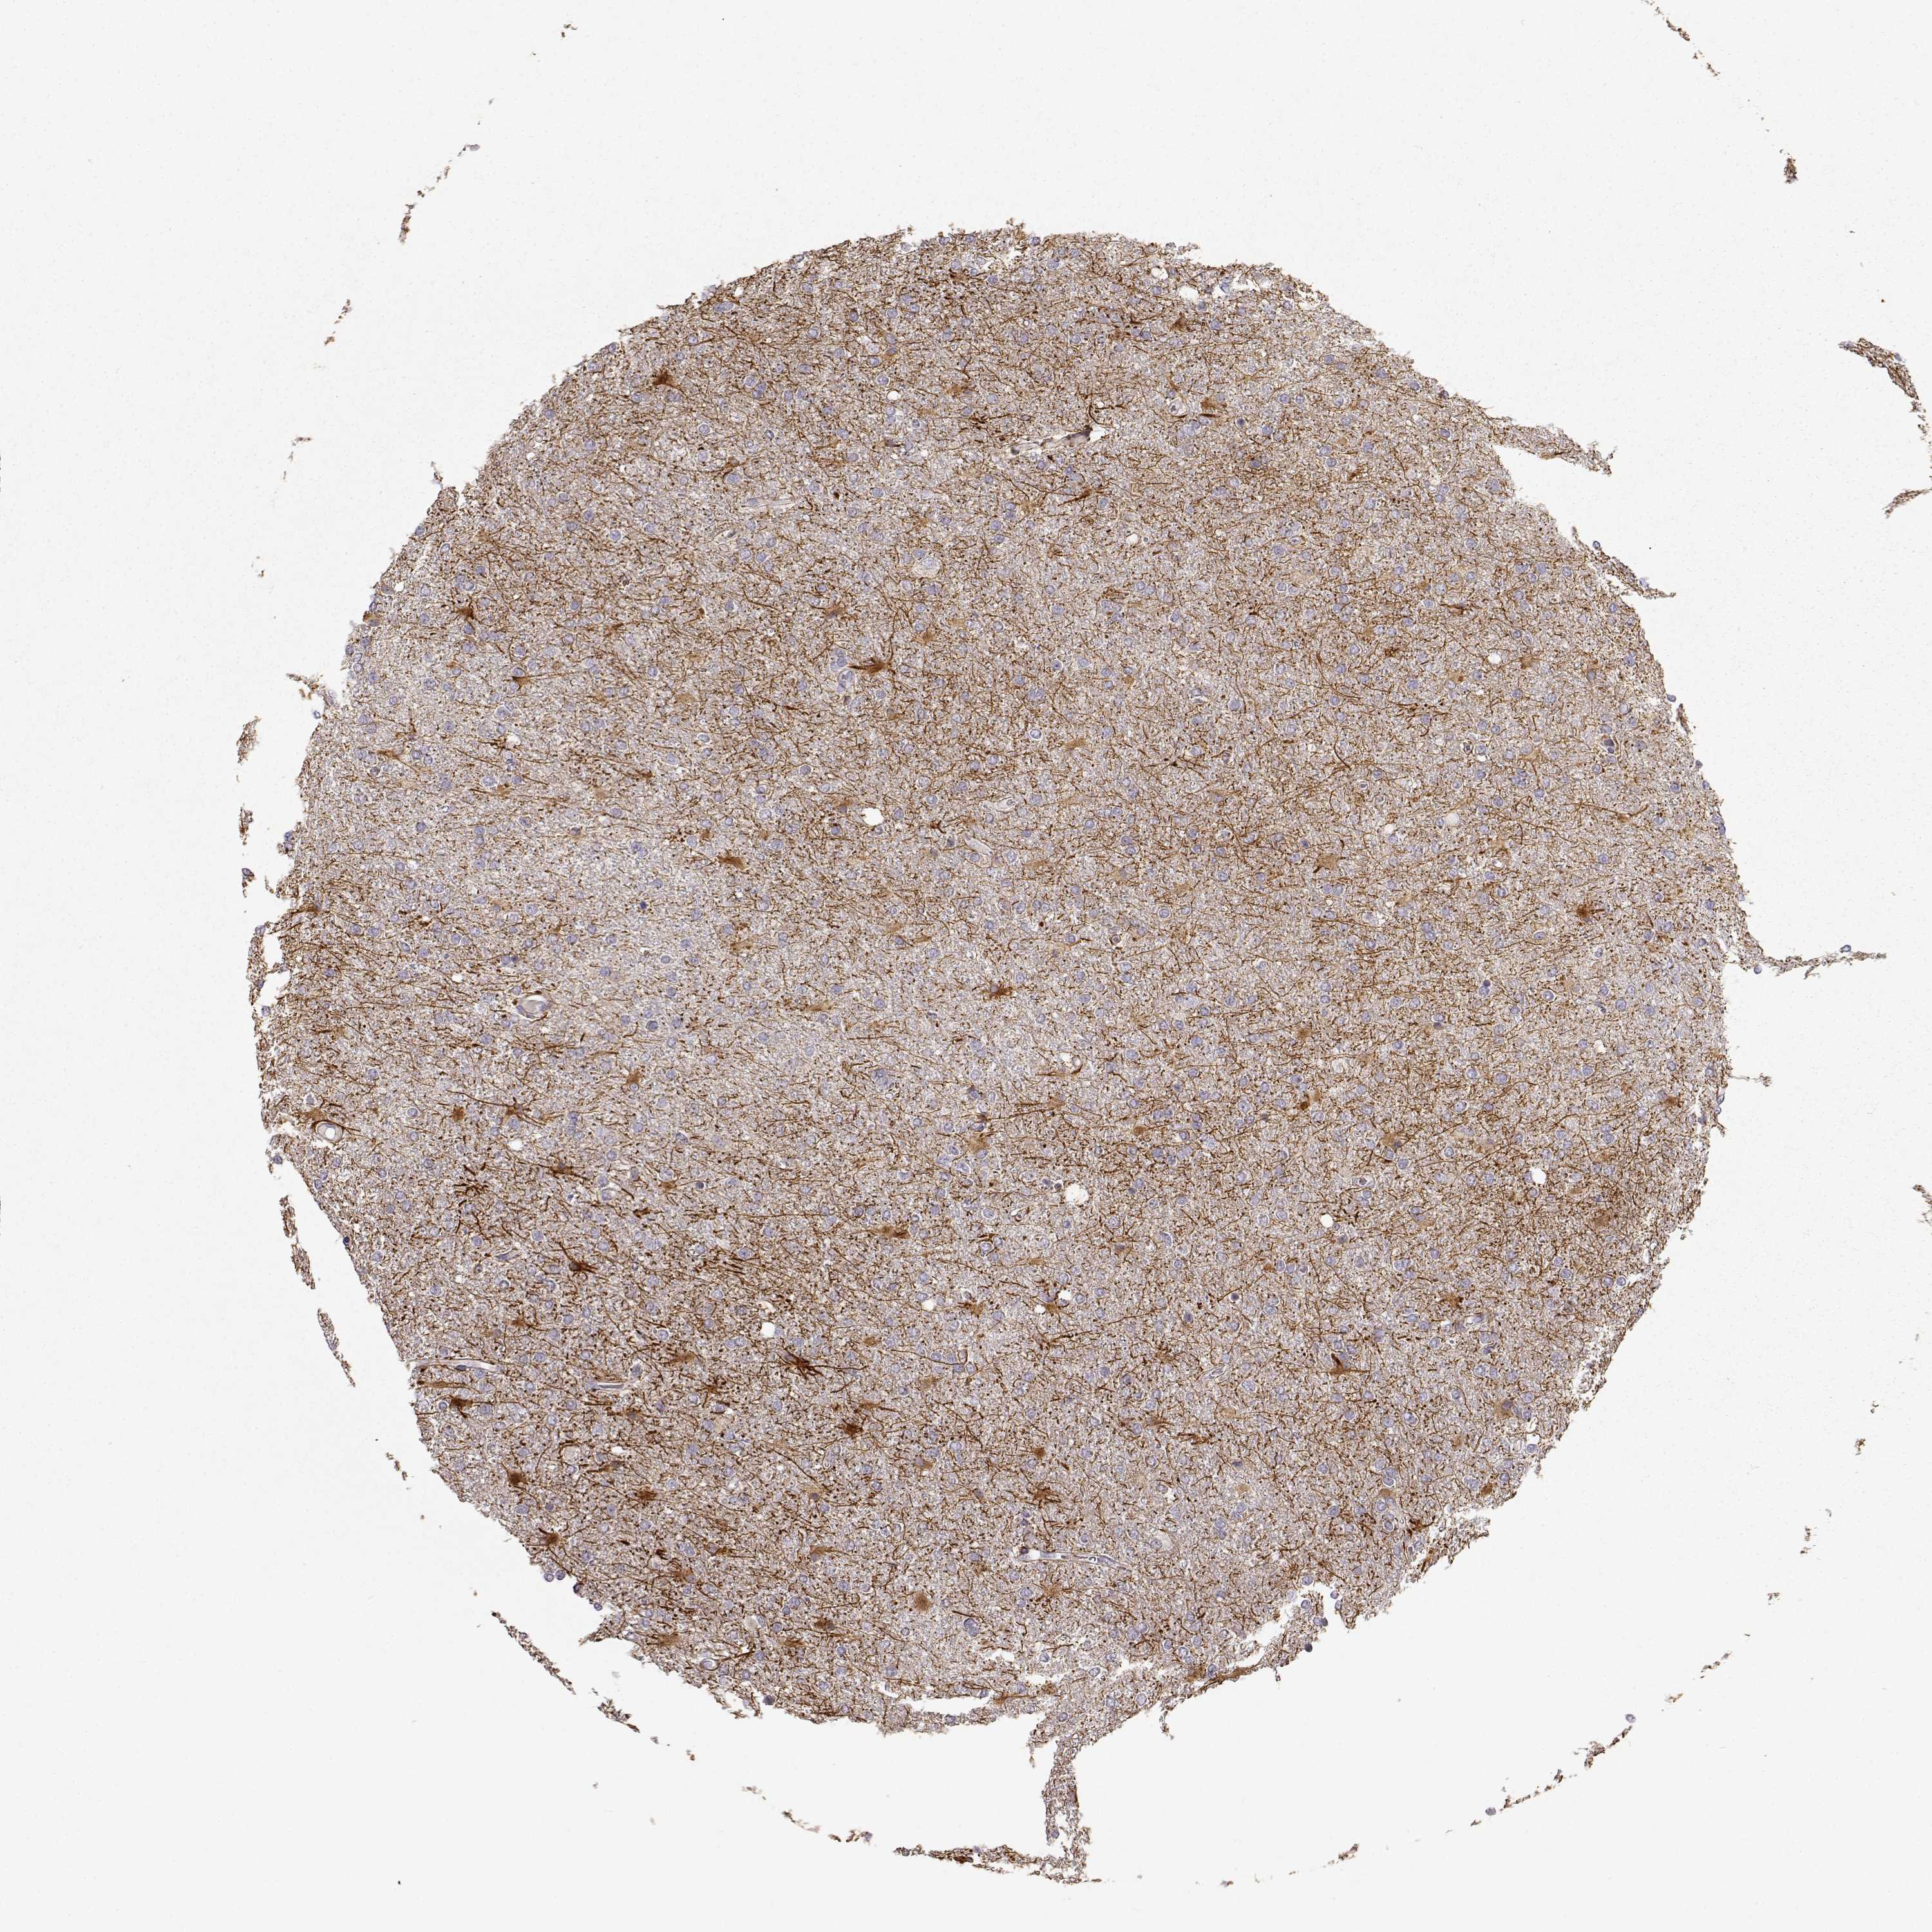

GLIOMA - Protein expressioni

A mouse-over function shows sample information and annotation data. Click on an image to view it in a full screen mode. Samples can be filtered based on level of antibody staining by selecting one or several of the following categories: high, medium, low and not detected. The assay and annotation is described here.

Note that samples used for immunohistochemistry by the Human Protein Atlas do not correspond to samples in the TCGA dataset.

Antibody stainingi

Antibody staining in the annotated cell types in the current human tissue is reported as not detected, low, medium, or high, based on conventional immunohistochemistry profiling in selected tissues. This score is based on the combination of the staining intensity and fraction of stained cells.

Each image is clickable and will lead to virtual microscopy that enables deeper exploration of all samples and also displays staining intensity scores, fraction scores and subcellular localization as well as patient and tissue information for each sample.

Antibody HPA045396

Antibody HPA070524

Antibody CAB025331

Glioma, malignant, High grade

Glioma, malignant, Low grade